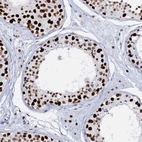

Immunohistochemical staining of human colon shows strong nuclear positivity in glandular cells.